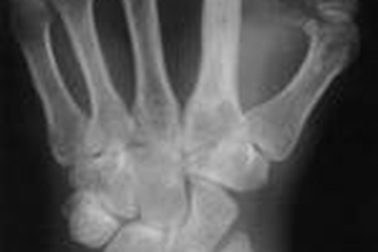

Bệnh viêm tủy xươngViêm tủy xương là chứng viêm mô xương thường bắt nguồn từ nhiễm trùng, có thể ảnh hưởng đến người ở mọi lứa tuổi. Nếu không được chữa trị, bệnh sẽ làm các khớp xương cứng lại hoặc phá hỏng xương.